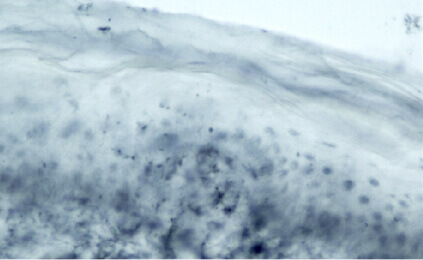

Direct Visualization

This test enables direct visualization and quantification of the terminal branches within the skin of a peripheral nerve.

Gauge Health

The structural integrity of the small nerve fibers is assessed. Then, they are counted to gauge the health of the nerves.

Nerve Fiber Count

A decrease in the number of small nerve fibers indicates the presence of established diseases, and the severity escalates as the count decreases